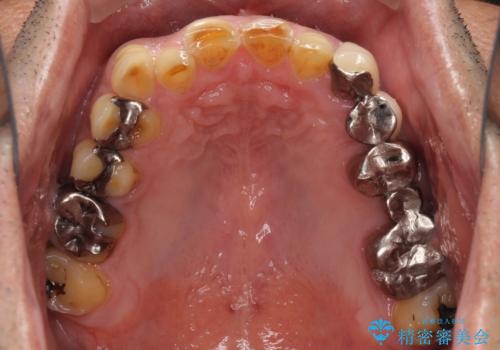

反対咬合ですり減った前歯とむし歯だらけの奥歯 総合歯科治療

- すり減った前歯や奥歯の銀歯を気にして来院された患者様です。

骨格的な反対咬合により上顎前歯の先端が顕著にすり減っている状態でした。

奥歯の欠損が散見されており、銀歯の装着されている歯も多いため、ワイヤー矯正にて歯列を調整し、その後オールセラミッククラウンにて補綴治療を行うこととしました。

反対咬合改善には奥歯の咬み合わせをしっかりと改善させることが必要となりますが、奥歯に欠損が多いため、矯正治療が難航することが予想されます。